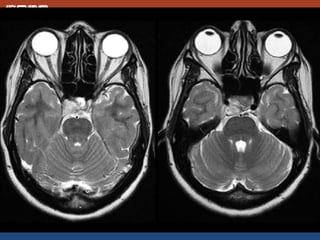

#Germinoma

• 5-25 yrs

• AKA dysgeminoma, intracranail seminoma

• MC at stalk and hypothalamus and pineal

region

• Crawls along floor of the 3rd vent

• Ddx: LCH, craniopharyngioma

• Adult: sarcoid, lymphoma